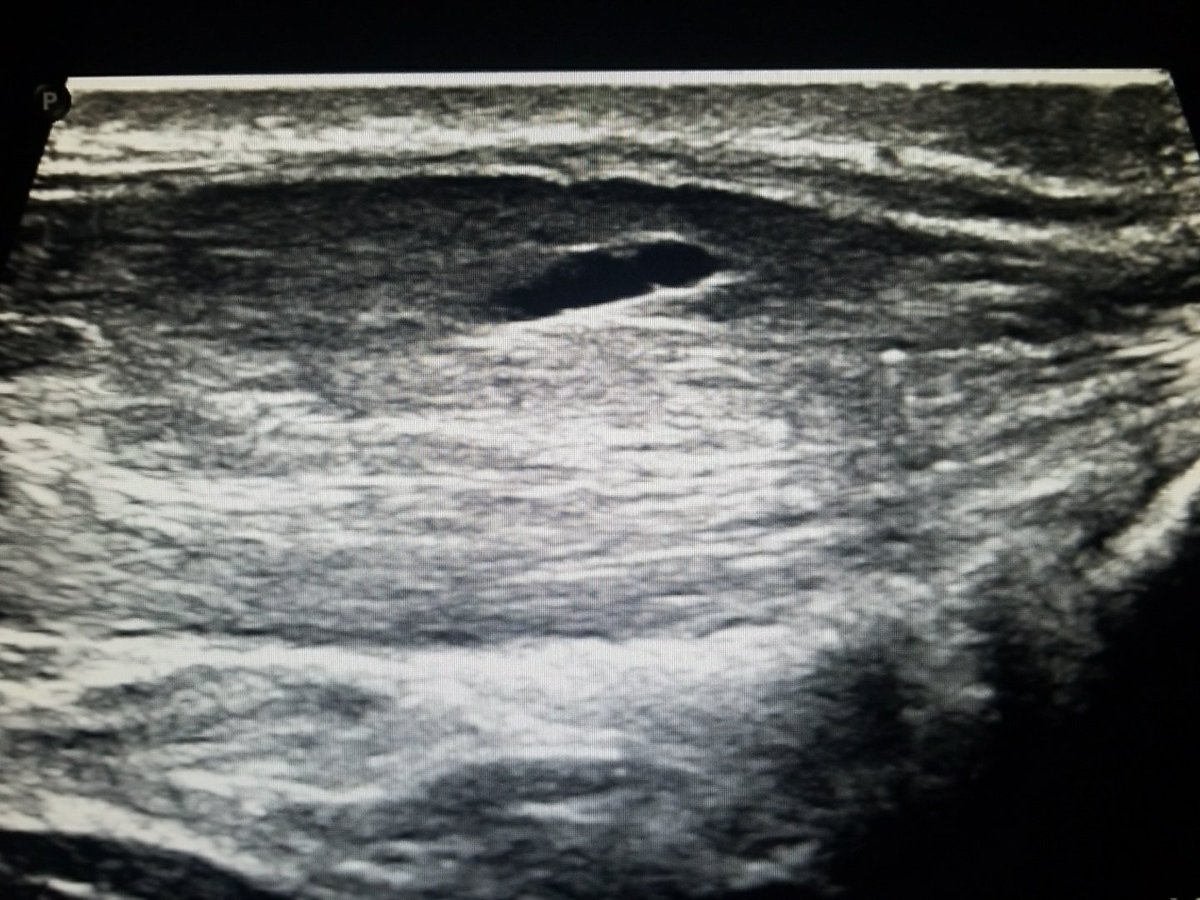

Ultrasound of the posterior hip/upper thigh structures and their relationship to one another. #hamstring #sciatic #nerve #msk #ultrasound linkedin.com/feed/update/ur…